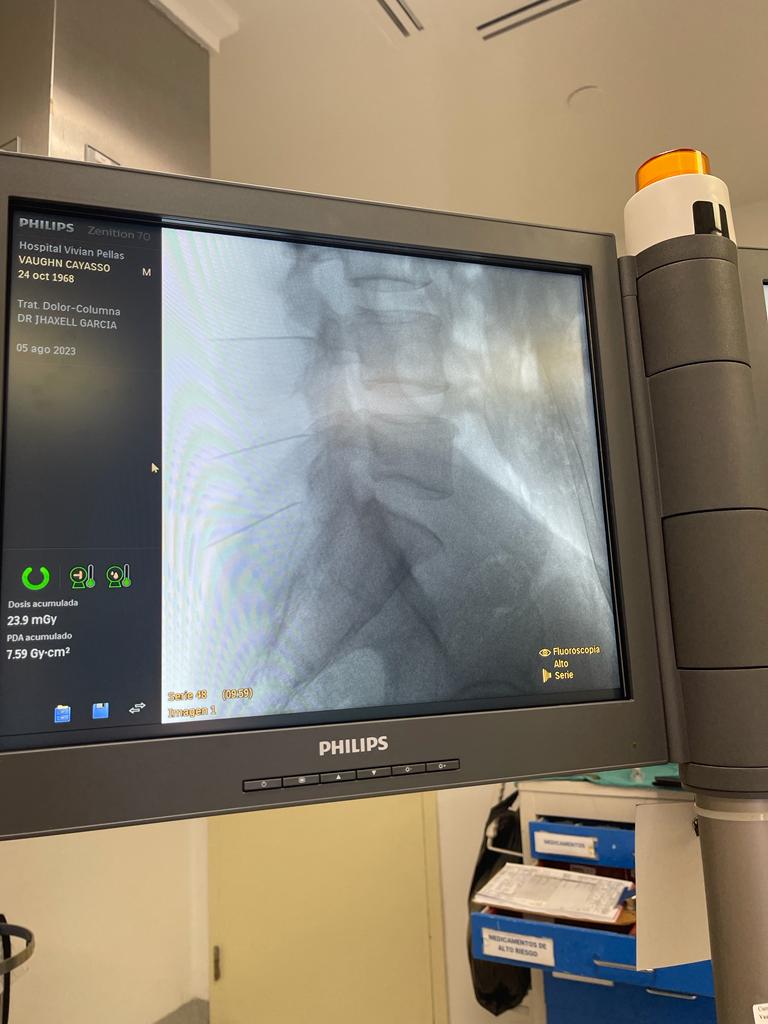

3. Rizólisis (Ablación por radiofrecuencia)

¿Qué es?

Procedimiento no invasivo que utiliza radiofrecuencia para desactivar nervios que transmiten dolor crónico en la columna.

Rizólisis (Ablación por Radiofrecuencia)

Técnica mínimamente invasiva para tratar el dolor crónico articular de la columna

La rizólisis es un procedimiento no quirúrgico que utiliza energía de radiofrecuencia para inactivar de forma selectiva los nervios responsables de transmitir dolor desde las articulaciones facetarias de la columna.